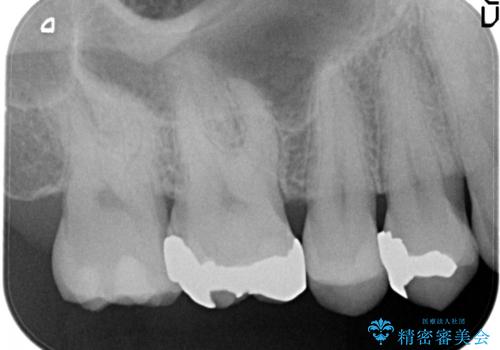

- 金属のインレーを除去を希望されて来院されました。

セラミックインレーにて治療を行なっております。

e-max プレスインレーにて修復治療を行っているため適合性及び審美性の高い治療を行うことができます